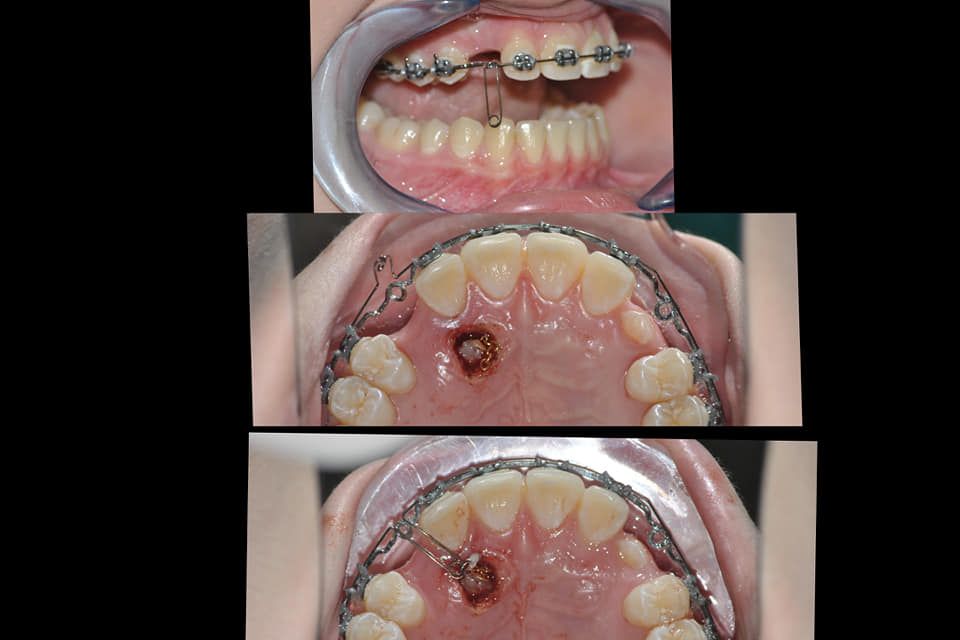

Il dottor Gianluca del Vecchio si occupa esclusivamente di ortognatodonzia, grazie anche alla collaborazione multidisciplinare di una équipe davvero entusiasmante e all’utilizzo di strumenti diagnostici e terapeutici all’avanguardia in ortognatodonzia. Particolare è la sua capacità di condurre i giovani pazienti ad affrontare, nella massima sicurezza emotiva e clinica, qualsiasi eventuale condizione di dolore derivante, ad esempio, da carie o da altre patologie, ma soprattutto di risolvere tutte quelle condizioni di “denti storti”, così spesso causa di disagio psicologico o di fenomeni deprecabili, quale il bullismo.

Il dottore ha acquisito una concezione quanto più pratica e moderna della disciplina e utilizza apparecchietti di diversi colori di tipo mobile e fisso, ma anche terapie sia estetiche che invisibili, fiore all’occhiello di poche realtà in Italia. Per terapie estetiche e invisibili si intendono quelle in grado di spostare i denti, senza che traspaia nulla dalla bocca o con stelline e fili bianchi, esattamente come i denti del paziente.

Ma ancora di più l’équipe è in grado di offrire un servizio davvero unico: la tecnica dei retainer attivi. Questa consiste in fili o bottoni che si incollano dietro i denti e che, quindi, nascondono completamente la terapia. Questo tipo di prestazioni aiuta a superare la grande difficoltà psicologica, che spesso si insinua anche negli adulti, di dover spostare i propri denti per un sorriso perfetto: si consideri che tale difficoltà non viene affrontata, il più delle volte, proprio per l’imbarazzo che una apparecchiatura ortodontica genera in chi la usa. Queste tecniche, insieme alle mascherine invisalign invisibili di cui è provider ufficiale e agli attacchi in ceramica, sono tutte quotidianamente utilizzate presso i nostri reparti, in cui è possibile associarle in un discorso multidisciplinare a tutte le altre esigenze della odontoiatria classica.